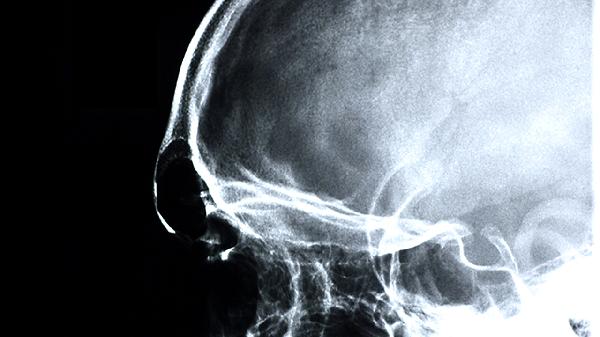

颅骨修补术后需密切观察6个月,定期复查CT评估钛网位置。保持头皮清洁,避免碰撞和抓挠。出现渗液、钛网轮廓显现等征兆时,尽早就医干预可降低完全外露风险。选择经验丰富的神经外科团队手术,能显著减少并发症发生。